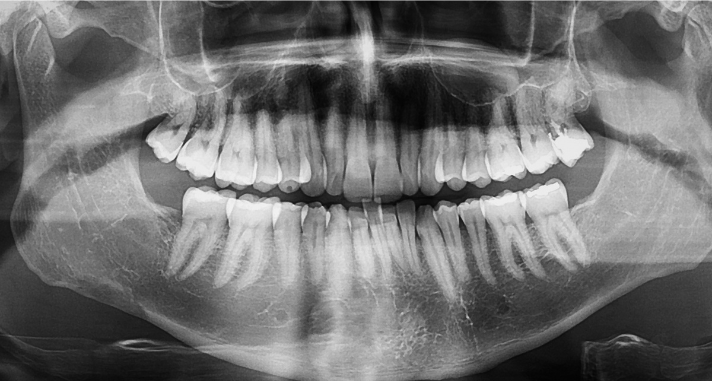

Instead of using old-school film, digital x-rays use an electronic sensor that sends a high-resolution image of your mouth directly to our computer screen. It happens almost instantly.

This tech allows us to zoom in, change the contrast, and see tiny details that would be invisible on a small piece of blurry film. We can spot a small cavity starting under an old crown or see the exact position of a wisdom tooth before it starts causing trouble for a student at West High.

The FDA notes that dental x-rays are essential for finding problems that a physical exam just can’t catch, such as infections inside the jawbone or tumors. By using the digital version, we get the best possible view with the least amount of risk.

See Your Smile in High Definition

We believe that when you can see what we see, you feel more in control of your health. No more guessing—just clear, digital proof of what’s happening under the surface.